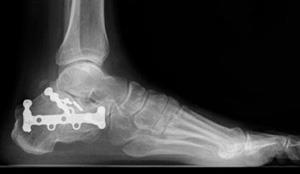

In this X-ray, the bone fragments have been realigned and held in place with metal plates and screws.